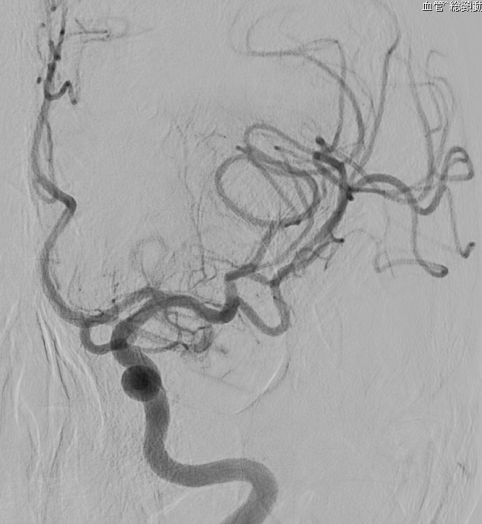

Apoplexy 21

【術前】

Apoplexy 22

【フローダイバーダー留置】

Apoplexy 23

【半年後】

フローダイバーター治療の放射線学的画像

ところが2015年に本邦においてフローダイバーターステント治療が導入されました。

動脈瘤内にコイルを充填することなく、非常に編み目を細かくしたステントで、これを正常血管に留置することで脳動脈瘤内に流入する血液量を減少させます。すると脳動脈瘤内の血液がうっ滞し、徐々に血栓化して脳動脈瘤が完全に閉塞します。半年後に約75%、1年後に約85%が完全に閉塞すると言われています。このような新しい治療法が動脈瘤治療において今後も期待されています。